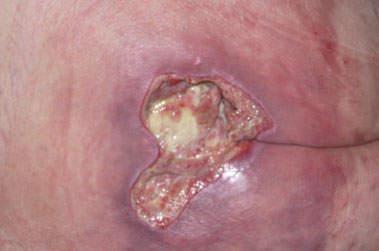

• Nécrose avec perte de substance importante, plaie ouverte profonde après élimination des tissus nécrotiques.

• Visualisation de l’os, fistule avec ou sans signe infectieux.